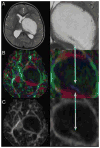

Methods: The authors present a retrospective review of their experience with 10 children presenting between 3 and 15 years of age with a thalamopeduncular syndrome. Formal preoperative MR imaging was obtained in all patients, and diffusion tensor (DT) imaging was performed in 9 patients. Postoperative MR imaging was obtained to evaluate the extent of tumor resection. A prospective analysis of clinical outcomes was then conducted by the senior author.

Results: Pilocytic astrocytoma was the pathological diagnosis in 9 cases, and the other was fibrillary astrocytoma. Seven of 9 pilocytic astrocytomas were completely resected. Radical surgery was avoided in 1 child after DT imaging revealed that the corticospinal tract (CST) coursed through the center of the tumor, consistent with the infiltrative nature of fibrillary astrocytoma as identified by stereotactic biopsy. In 8 patients, tractography served as an important adjunct for designing a surgical approach that spared the CST. In 6 cases the CSTs were pushed anterolaterally, making a transsylvian approach a poor choice, as was evidenced by the first patient in the series, who underwent operation prior to the advent of tractography, and who awoke with a dense contralateral hemiparesis. Thus, subsequent patients with this deviation pattern underwent a transcortical approach via the middle temporal gyrus. One patient exhibited medial deviation of the tracts and another had lateral deviation, facilitating a transtemporal and a transfrontal approach, respectively.